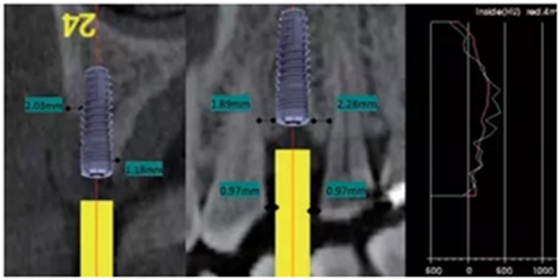

備孔

戴上導(dǎo)板逐級備孔注意導(dǎo)板的就位要準(zhǔn)確不晃動,備孔時(shí)應(yīng)通過充分的提拉鉆頭來獲得良好的冷卻。

圖3 戴上導(dǎo)板并按照操作說明書逐級備孔